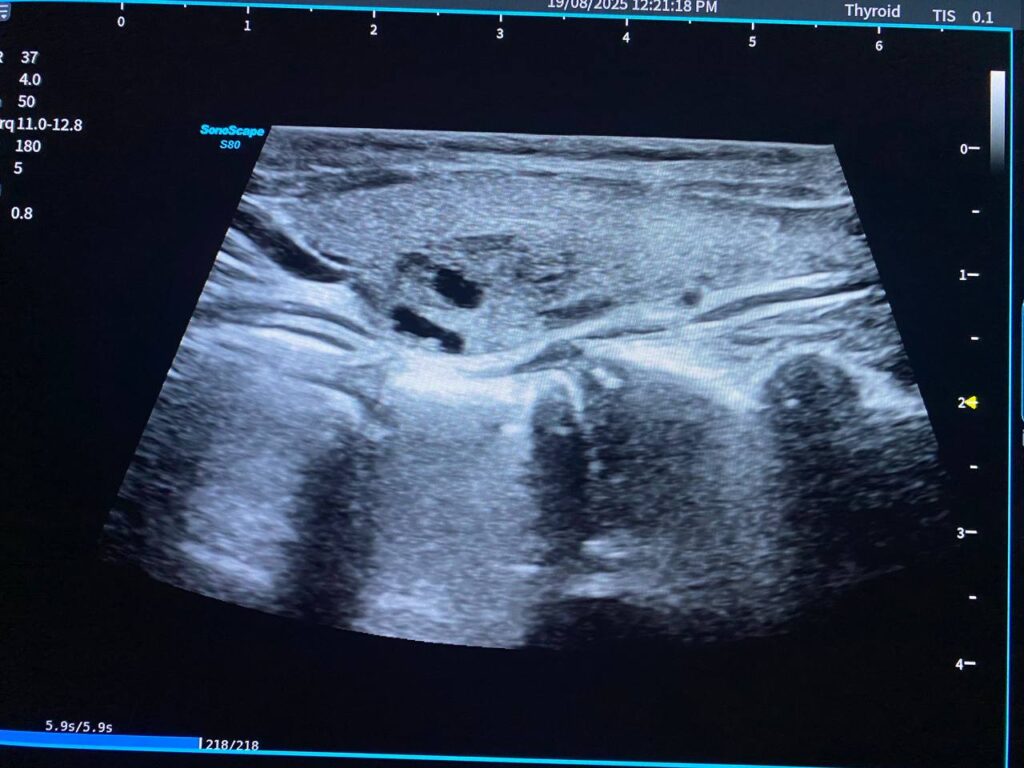

Right lobe size = 31x57x25mm, normal in texture, contain heterogenous circumscribed nodule 33x18mm, contain macrocalcification , mostly benign , TIRADS 3 , For short interval follow up

Left lobe size = 21.4x48x14mm, normal in texture, contain heterogenous circumscribed nodule 15.4×9.6mm , TIRADS 3 , and other nodule 10.8x5mm , contain micro calcification , TIRADS 3 , For short interval follow up

Isthmus 4.3mm, normal in texture, no focal lesion